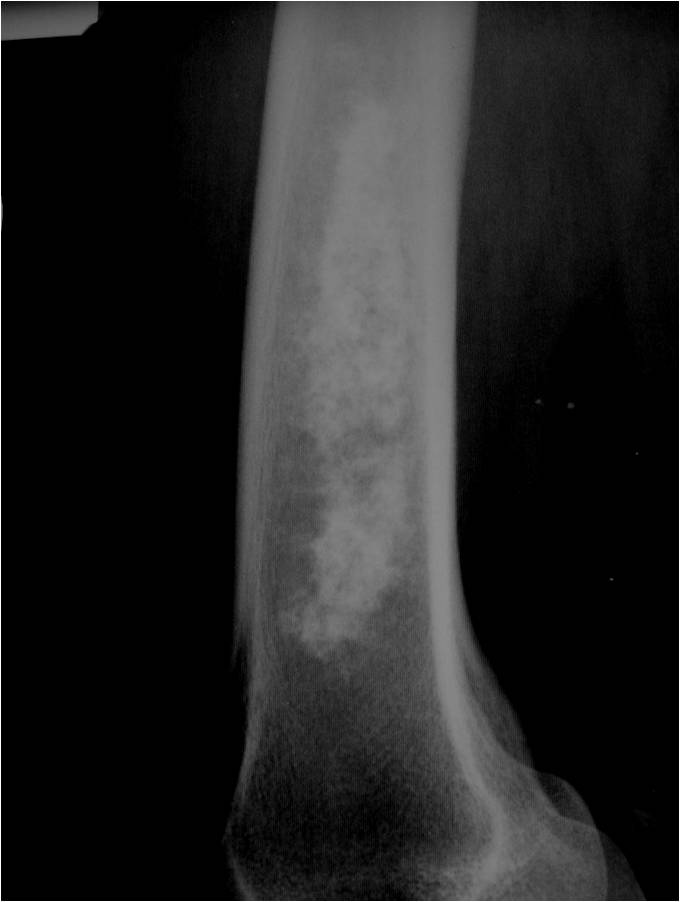

Radiographic Presentation

- Localized, radiolucent defect usually with punctate calcifications

- Calcifications are typical but not always present

- Matrix may demonstrate various degrees of calcification

- Calcifications are stippled, punctate, popcorn like calcifications and “Ring and Arc” calcifications

- Cartilage tumors grow in a lobular manner. The perimeters of the lobules undergo

- enchondral ossification that may calcify. If the entire perimeter of the lobule calcifies it appears

- radiographically as a “Ring”. If a portion of the perimeter of a lobule calcifies it forms an “Arc” on

- an X-ray.

Plain X-Ray:

- Geographic lytic lesion

- Central often metaphyseal in long bones

- Can be eccentric also

- Expansile remodeling with thinned cortex

- Chondroid matrix with calcifications in majority of tumors

- Approximately 20% have limited or no calcifications